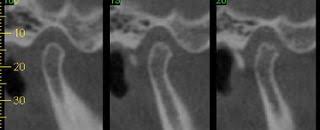

تستخدم أنواع أخرى من اختبارات الصور إلى جانب الأشعة السينية. مثل:

- التصوير بالرنين المغناطيسي – MRI: يعمل على إظهار الأنسجة الرقيقة كأنسجة مفاصل الفك للتأكد من وجودها في مكانها الطبيعي عند حركة الفك في أي اتجاه

- الطبوغرافيا باستخدام الحاسوب – CT: و التي تساعد على إظهار التفاصيل الدقيقة لعظام الفك.

اشعة مقطعيه لمفصل الفك